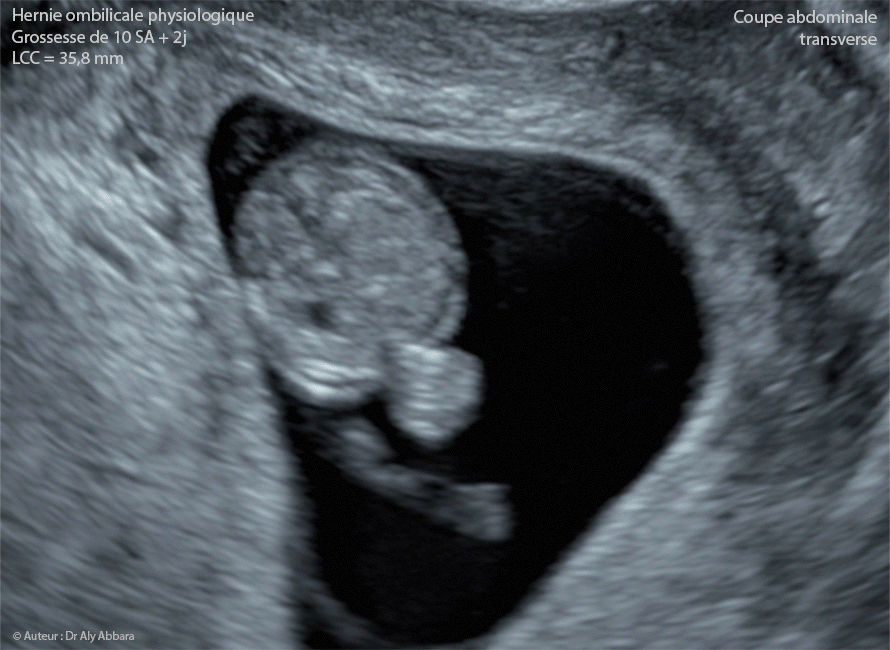

La hernie ombilicale est une affection abdominale courante caractérisée par la protrusion d'une partie de l'intestin à travers l'anneau ombilical. Hernie ombilicale et grossesse : des enjeux spécifiques

Qu'est ce qu'un hernie ombilicale ? La hernie est caractérisée par la sortie d'un organe ou d'une partie d'organe hors de la cavité où ils se trouvent habituellement FAQ sur la Hernie Ombilicale Durant la Grossesse 1 Hernie Ombilicale et Grossesse : Comment Éviter les Complications; Prévenir les Hernies Ombilicales Pendant la Grossesse : Conseils Essentiels pour les Futures Mamans; Grossesse et Hernie Ombilicale : Comprendre les Risques et les Solutions; Les Meilleures Stratégies pour Prévenir la Hernie Ombilicale Lors de la Grossesse

Hernie ombilicale pendant la grossesse causes et traitements Maternite. Hernie Ombilicale et Grossesse : Comment Éviter les Complications; Prévenir les Hernies Ombilicales Pendant la Grossesse : Conseils Essentiels pour les Futures Mamans; Grossesse et Hernie Ombilicale : Comprendre les Risques et les Solutions; Les Meilleures Stratégies pour Prévenir la Hernie Ombilicale Lors de la Grossesse La hernie ombilicale est une pathologie bénigne souvent causée par une prise de poids rapide.Elle se produit lorsque les muscles de la paroi abdominale ne sont pas assez forts pour contenir les organes internes, notamment l'intestin.